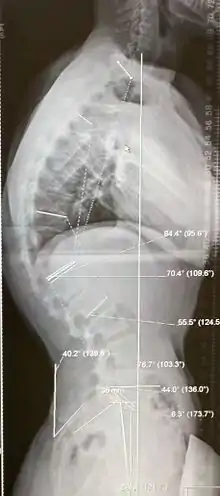

درجة الحداب يتم قياسها باستخدام طريقة زاوية كوب.

- ازدياد الحداب لأكثر من 70 درجة (بحيث لا يمكن الحد من التدهور باستخدام الدعامة) مصاحب لآلام شديدة لا تخف مع المسكنات أو العلاج التحفظي لمدة 6 شهور على الأقل.

نتائج بعض الأبحاث التي درست اختيار النوع والتقنية الجراحية المثلى

- تثبيت ودمج الفقرات من الجهة الخلفية للعمود الفقري باستخدام البراغي العنيقية للفقرات مع قطع العظم بطريقة سميث بيترسن يؤدي إلى تصحيح كبير للحداب الظهري، كما أن احتمالية وجود مضاعفات جانبية أقل، مقارنة بالتثبيت والدمج من الجهة الأمامية والخلفية باستخدام نظام هجين.

- التثبيت من الجهة الأمامية والخلفية لا يختلف عن التثبيت فقط من الجهة الخلفية عند مقارنة النتائج بالنظر إلى الصور الشعاعية.

- التثبيت من الجهة الخلفية باستخدام البراغي العنيقية للفقرات مع قطع العظم بطريقة بونتي بدون أي تدخل من الجهة الأمامية أعطى نتائج ممتازة لتصحيح الحداب.